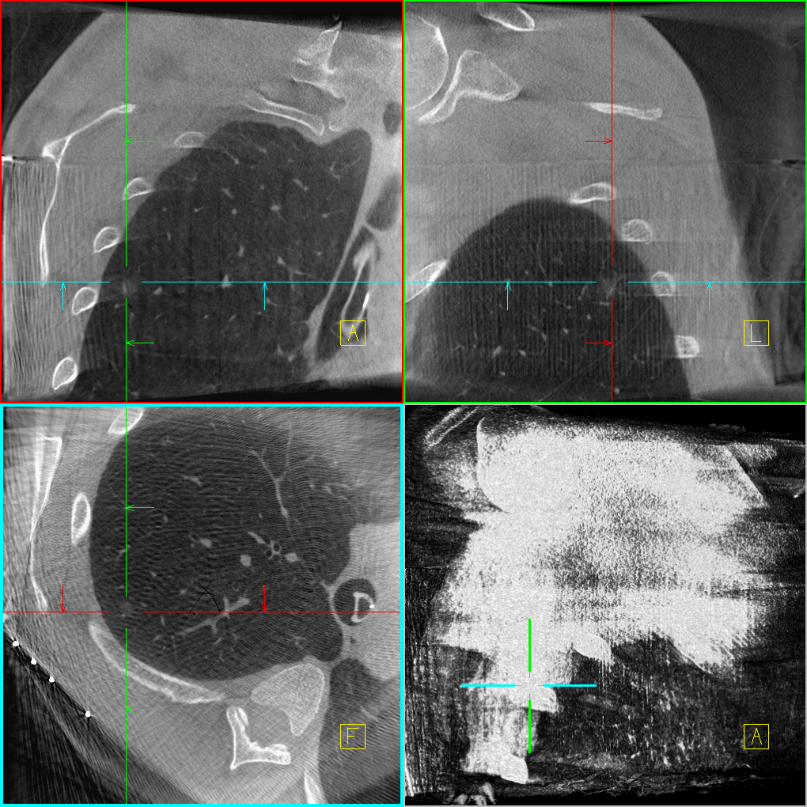

术前胸部CT